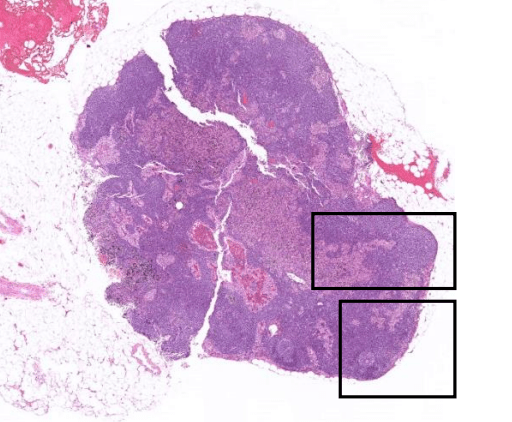

Pathology Micro-2

Tumor Description:

1. border(infiltrative到哪裡/circumscribed/capsule)

2. architecture

3. cell 長相

4. stroma

5. 其他周邊異常

(circumscribed/infiltrative)

localized type: circumscribed